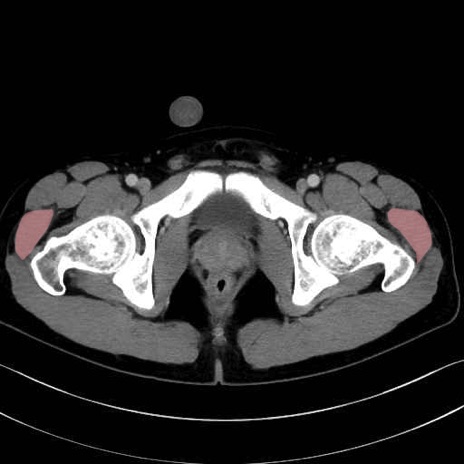

中殿筋 (Gluteus medius)